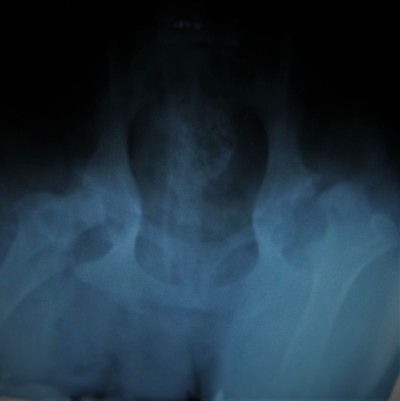

Más allá de las radiografías hechas con fines diagnósticos en los casos de animales enfermos en nuestra clínica tratamos de aplicar también el sistema del examen radiológico preventivo para diagnosticar enfermedades hereditarias, como por ejemplo la ¨displasia¨de cadera.

En nuestra clínica existe la posibilidad de enviar los rayos X a Inglaterra o a los Estados Unidos, a radiólogos y ortopedas especiales cuando una seguanda opinión se crea necesaria.

Se trata de un servicio de segunda opinión de los Estados Unidos que nos permite mandar los rayos X al extranjero , para tener la opinión de veterinarios expertos en la radiología.